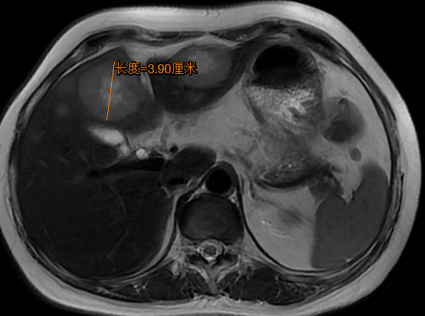

MRI:胃窦壁不规则增厚,较厚处约2.4cm;肝门部、腹膜后多个淋巴结显示,大者短径约1.5cm;肝内多发转移,大者约3.9*4.0cm(图2)。

图2. 腹部MRI检查